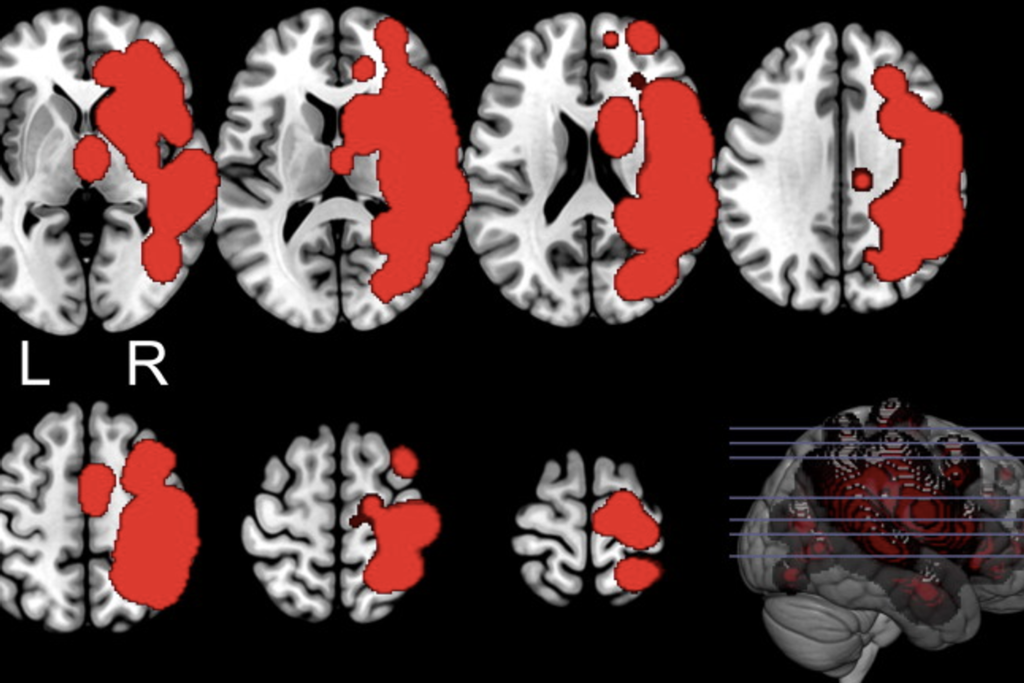

Angio-scanner : coupes étagées montrant (en rouge) les lésions de l’hémisphère cérébral droit. L : gauche.

R : droit.

C’est l’histoire d’un homme de 76 ans, droitier, victime d’un accident vasculaire cérébral (AVC) provoqué par un caillot ayant obstrué une artère, privant ainsi une partie de son cerveau de sang et d’oxygène. Cet AVC dit ischémique a entraîné une large lésion qui touche à la fois la substance grise corticale (la fine couche externe, le cortex), la substance grise sous-corticale (plus en profondeur), ainsi que la substance blanche de l’hémisphère droit. Cette atteinte a laissé le patient hémiplégique du côté gauche et insensible de ce même côté : on parle alors d’hémianesthésie.

En 2012, une équipe italienne a publié dans la revue Cortex une étude qui a précisé les bases neuroanatomiques de la somatoparaphrénie. Jusqu’alors, les rares travaux disponibles étaient contradictoires. Pour dépasser ces incertitudes, des chercheurs en psychologie, neurologie et neuropsychologie de l’Université de Milan ont comparé deux groupes de patients avec lésion cérébrale droite. Onze patients présentaient une somatoparaphrénie et onze autres en étaient indemnes, mais tous souffraient des mêmes troubles associés (hémiplégie, négligence spatiale et anosognosie). Ce protocole permettait d’isoler ce qui relève spécifiquement de la somatoparaphrénie.

Les résultats ont montré qu’en cas de somatoparaphrénie, les lésions affectaient un réseau cérébral plus vaste et plus profond. Tous les patients présentaient des atteintes fronto-temporo-pariétales (régions associées à la paralysie, à la négligence spatiale et à l’anosognosie). Mais ceux présentant une somatoparaphrénie avaient de surcroît des lésions de la substance blanche de l’hémisphère droit (bras postérieur de la capsule interne, corona radiata, faisceau longitudinal supérieur) ainsi que des atteintes de la substance grise sous-corticale, à savoir des noyaux gris comme les ganglions de la base, le thalamus et l’amygdale.